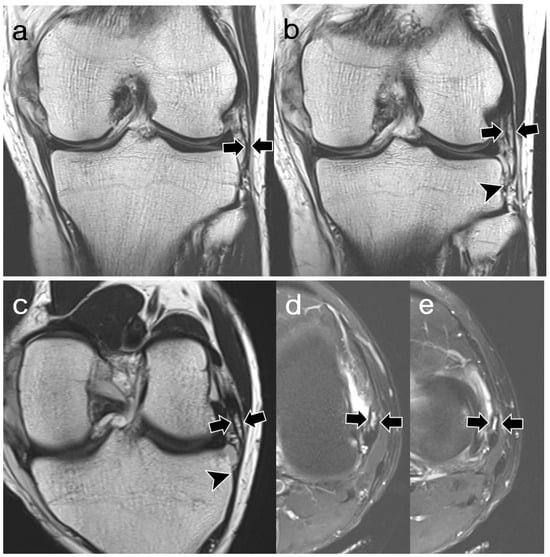

3.2. ALL Visibility

3.3. ALL Morphology